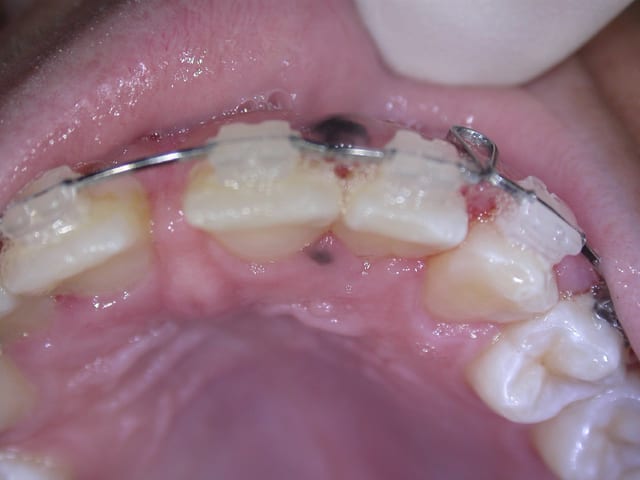

J'ai une patiente de 14 ans, martiniquaise, qui a deux taches noires sur la gencive d'apparition +- récente ( elle ne les avait pas il y a un an). J'ai un vague souvenir de coloration gingivale brune chez les patients de couleur noire, mais il me semble que c'était généralisé et pas sous forme de tache comme ici.

Je vous joins les photos...et merci d'avance pour vos lumières!!

Bon le chirurgien étant en vacances, je n'ai pas eu le résultat extact...mais ce n'était rien, tache "ethnique"...

Résultats aujourd'hui: pigmentation lenticulaire essentielle de la gencive...rien de méchant et je suis effectivement rassurée pour ma patiente!